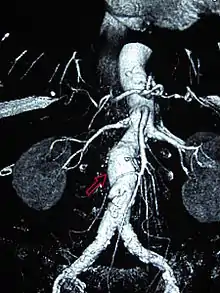

Abdominal aortic aneurysm

Abdominal aortic aneurysms (AAAs) are more common than their thoracic counterpart. One reason for this is that elastin, the principal load-bearing protein present in the wall of the aorta, is reduced in the abdominal aorta as compared to the thoracic aorta. Another is that the abdominal aorta does not possess vasa vasorum, the nutrient-supplying blood vessels within the wall of the aorta. Most AAA are true aneurysms that involve all three layers (tunica intima, tunica media and tunica adventitia). The prevalence of AAAs increases with age, with an average age of 65–70 at the time of diagnosis. AAAs have been attributed to atherosclerosis, though other factors are involved in their formation.[7]

The risk of rupture of an AAA is related to its diameter; once the aneurysm reaches about 5 cm, the yearly risk of rupture may exceed the risks of surgical repair for an average-risk patient. Rupture risk is also related to shape; so-called "fusiform" (long) aneurysms are considered less rupture-prone than "saccular" (shorter, bulbous) aneurysms, the latter having more wall tension in a particular location in the aneurysm wall.[9]

Before rupture, an AAA may present as a large, pulsatile mass above the umbilicus. A bruit may be heard from the turbulent flow in the aneurysm. Rupture may be the first sign of AAA. Once an aneurysm has ruptured, it presents with classic symptoms of abdominal pain which is severe, constant, and radiating to the back.[9]

The diagnosis of an abdominal aortic aneurysm can be confirmed by the use of ultrasound. Rupture may be indicated by the presence of free fluid in the abdomen. A contrast-enhanced abdominal CT scan is the best test to diagnose an AAA and guide treatment options.[10]